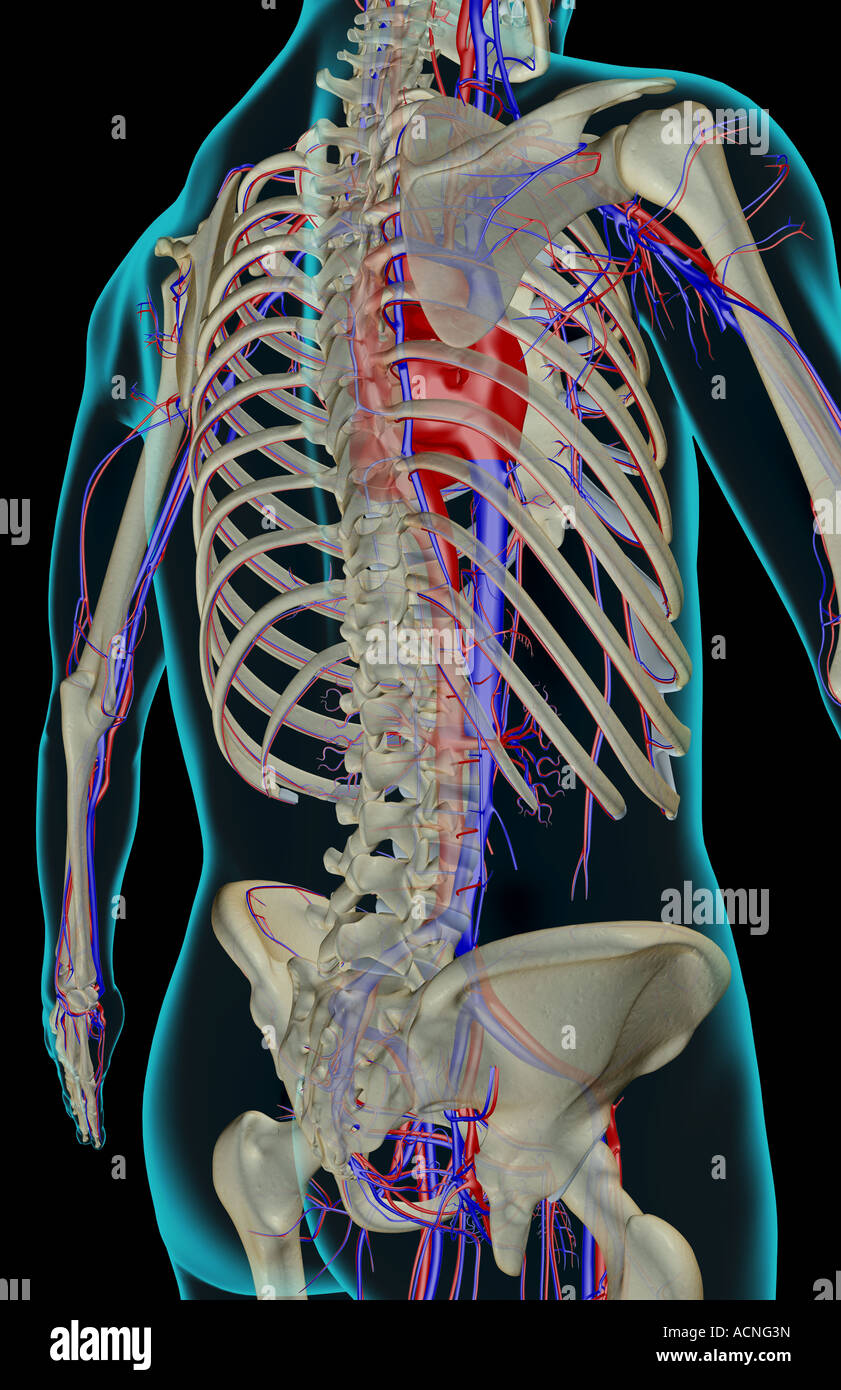

RMETMN27–Darstellung der Blutversorgung und Skelett-Struktur der Unterschenkel, durch die Haut sichtbar.

RMETMNMF–Darstellung der Blutversorgung und Skelettsystem an den Unterschenkeln, durch die Haut sichtbar.

RMETMP9E–Darstellung der Blutversorgung und Skelett-Struktur der Unterschenkel, durch die Haut sichtbar.